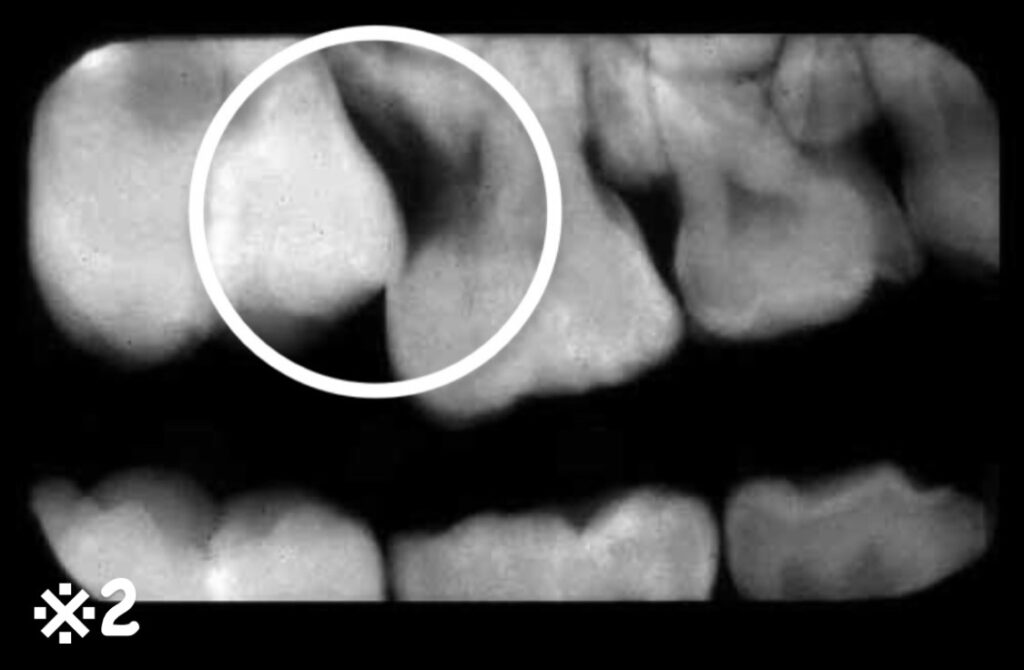

第1大臼歯の異所萌出も6歳以降によくみられ、レントゲン撮影で発見されることもあります。

第1大臼歯の手前にある第二乳臼歯の下にもぐりこむことによって、乳臼歯が早くに抜け落ちてしまったり、根の一部が消失してしまうことがあります。(※2)

これらは、いずれも歯並びや噛み合わせの異常につながります。